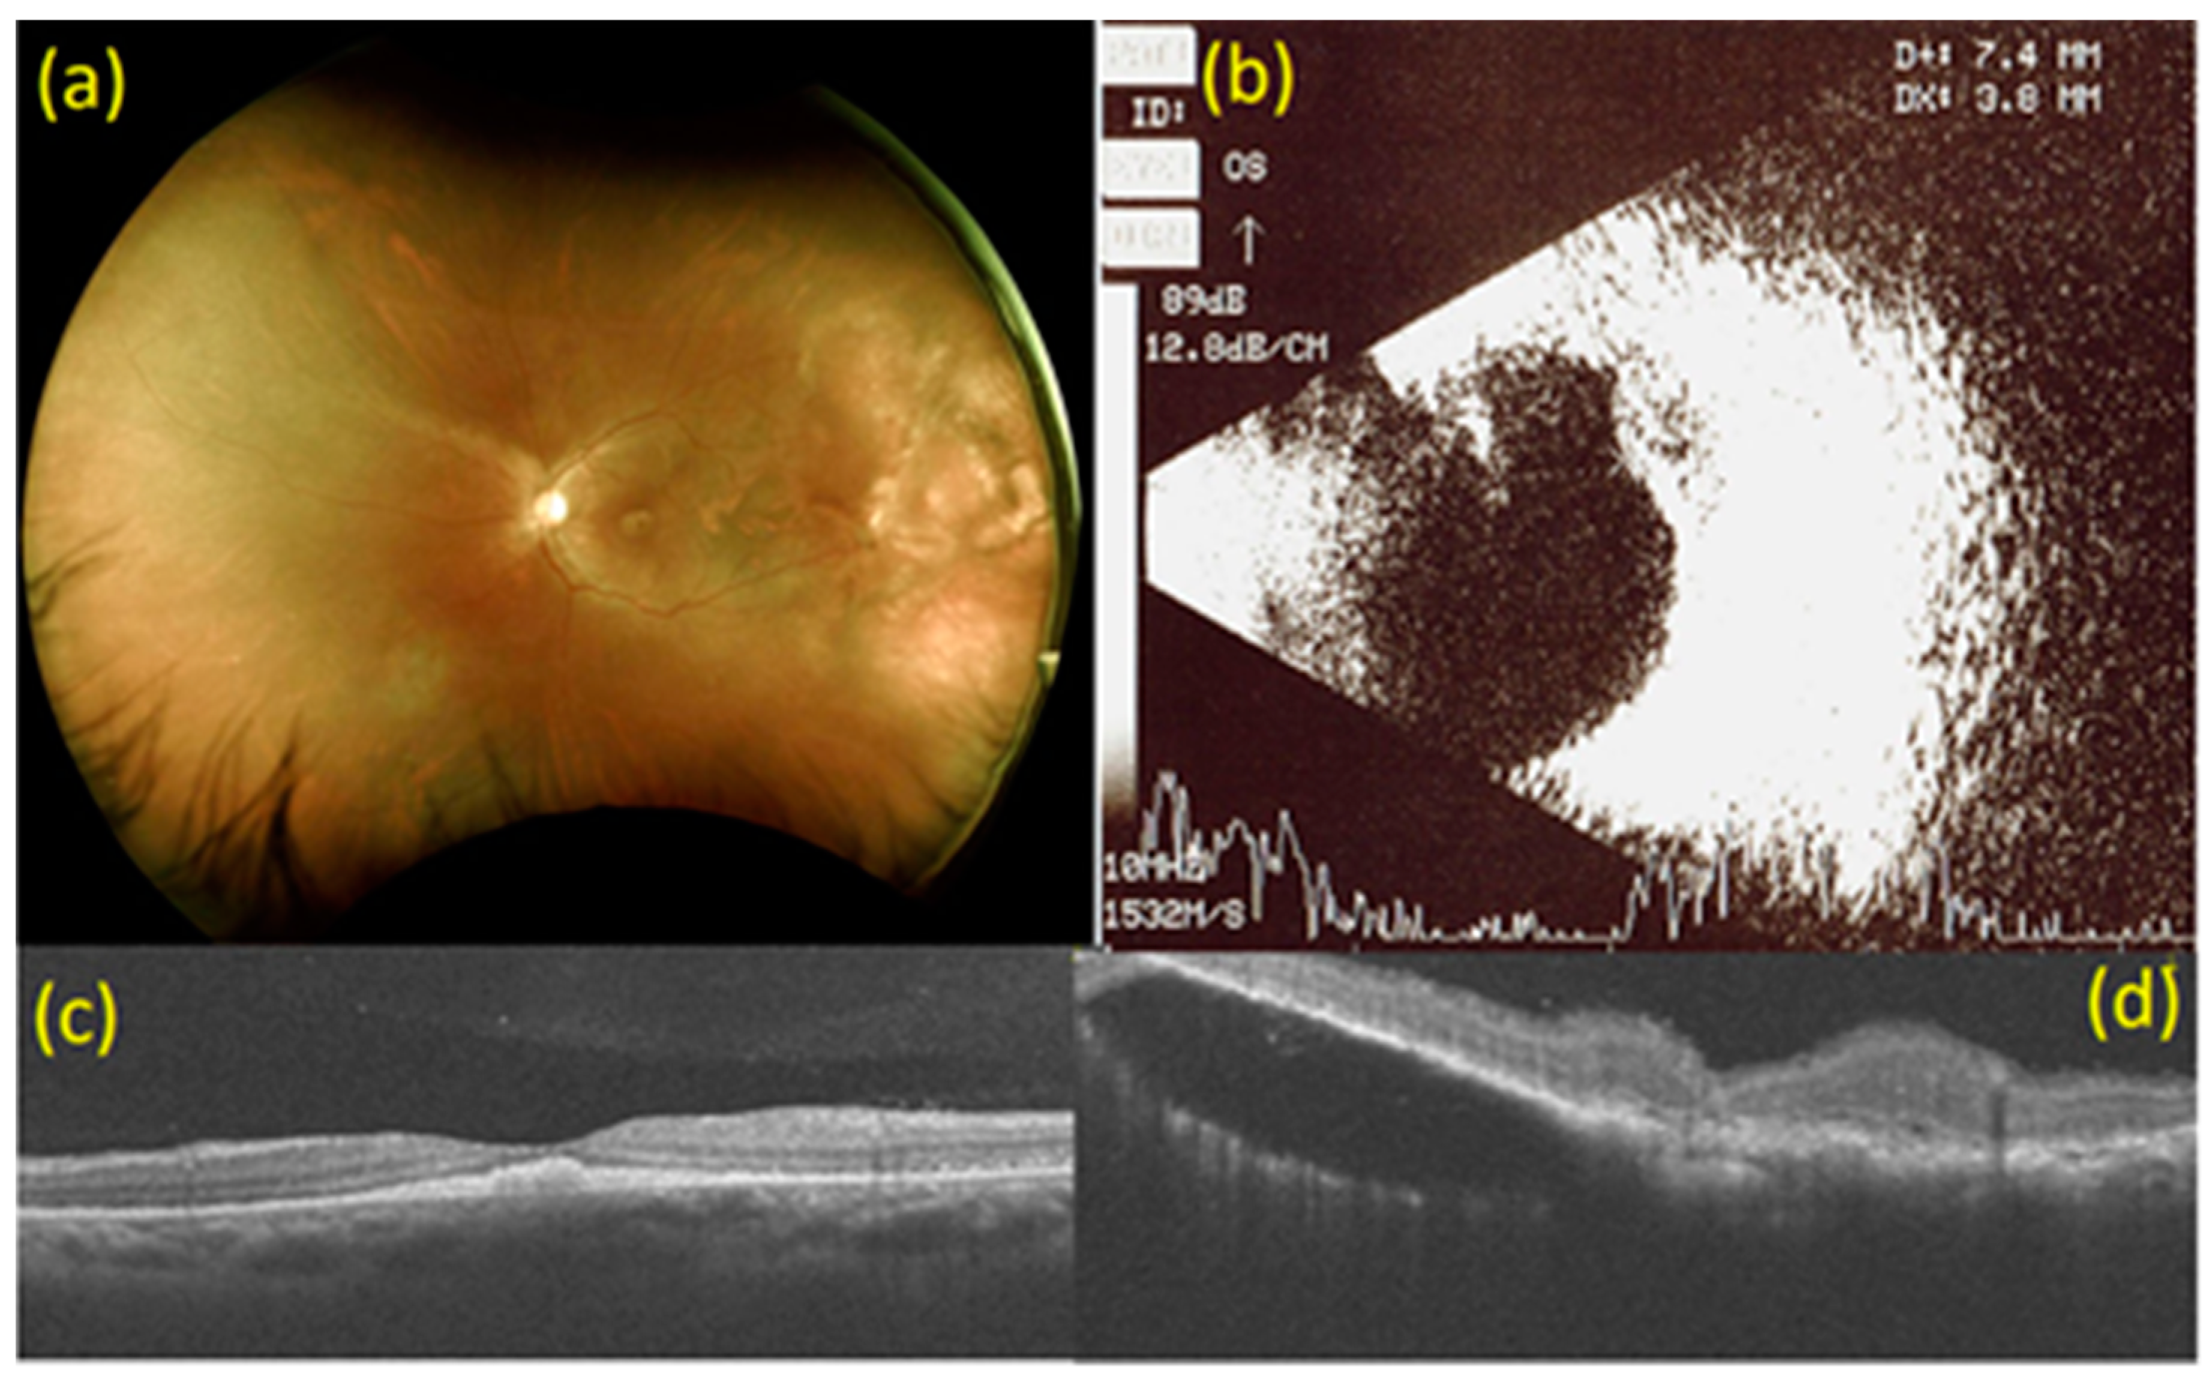

2. Case Report